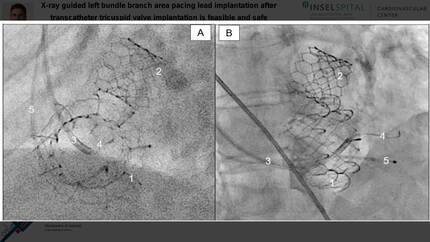

X-ray guided left bundle branch area pacing lead implantation after transcatheter tricuspid valve replacement is feasible and safe